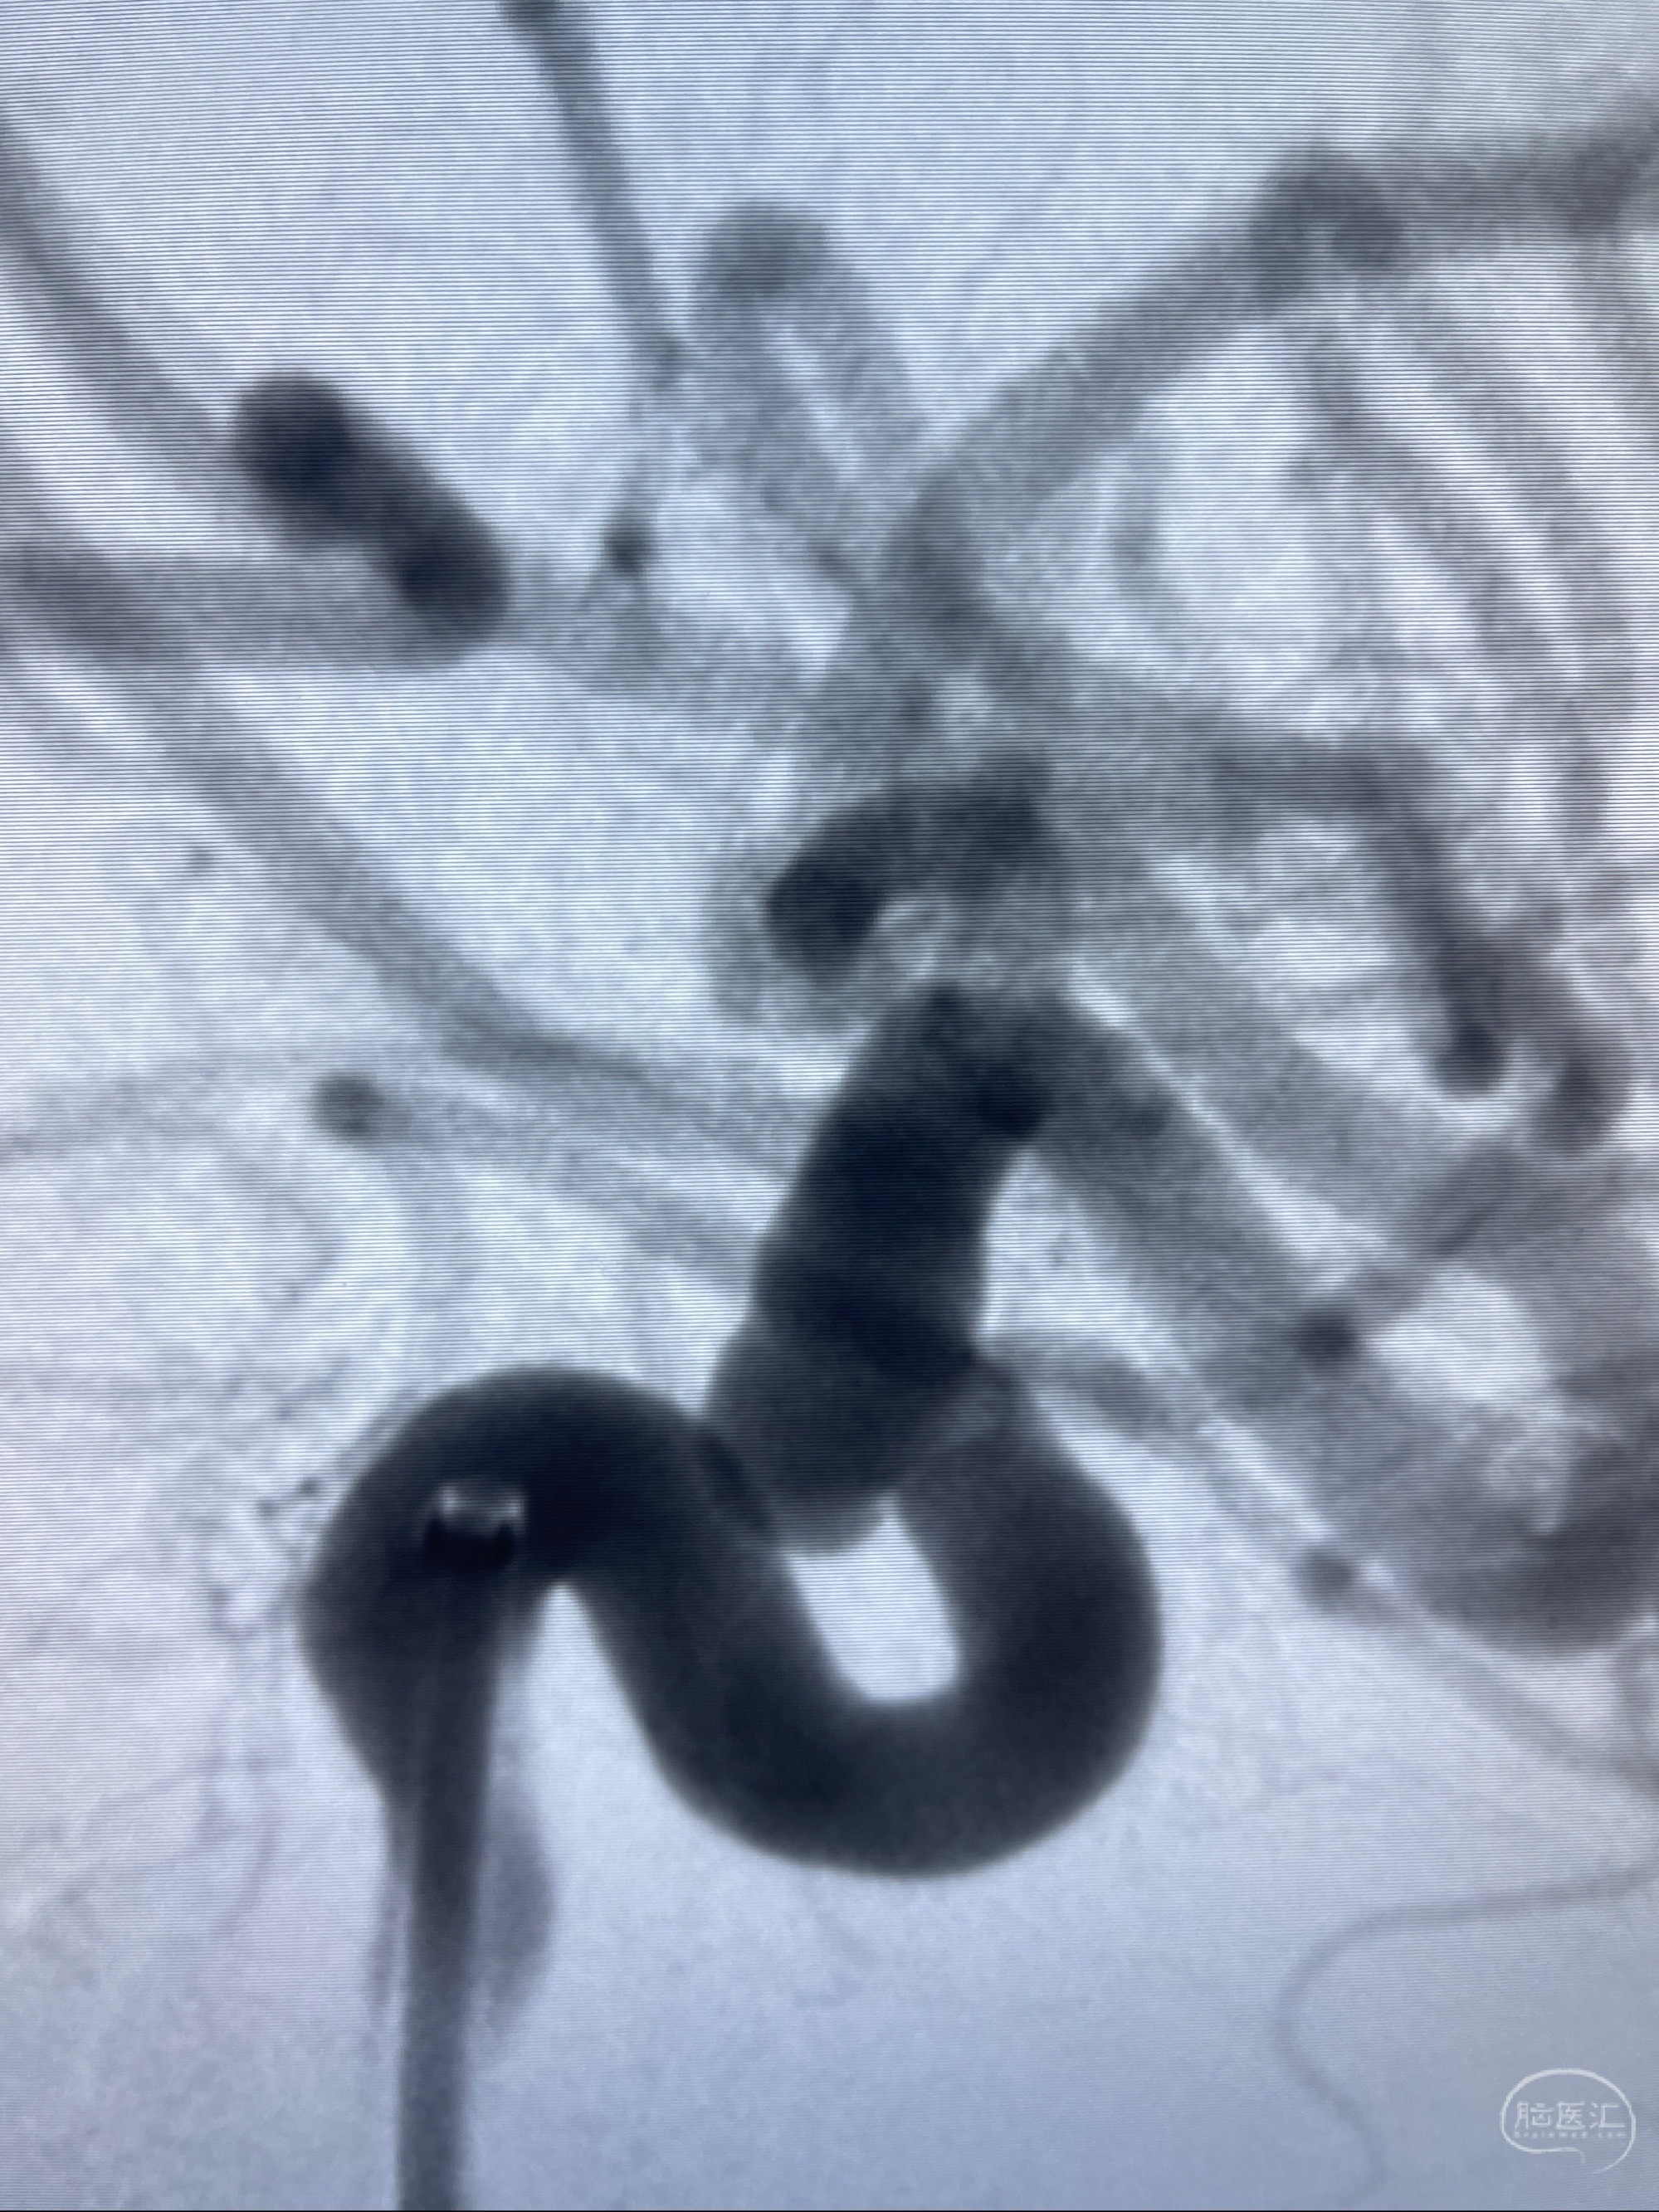

2023-08-01全麻下行双侧颈眼动脉瘤支架辅助栓塞

- pipeling4.5-20mm

- pipeline 4.0-20mm

手术顺利,麻醉苏醒佳,遵嘱动作

术后即刻CT